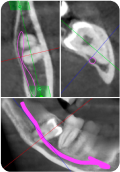

Удаление ретенированных и дистопированных третьих моляров

Что будет в модуле:

Атравматичное удаление ретенированных третьих моляров

Классификация ретенции третьих моляров

Разрезы и типы лоскутов

Техника остеоэктомии

Навыки на уровне челюстно-лицевой хирургии: от удаления зачатка ретенированного нижнего третьего моляра до удаления горизонтально расположенных зубов.